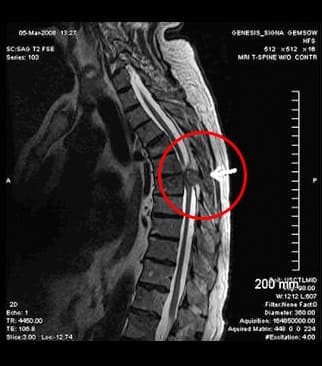

Το ΗΚΓ έδειξε ότι η υγεία μου ήταν μια χαρά. Έκανα πλήρεις εξετάσεις στο νοσοκομείο και ανακάλυψα ότι είχα θωρακική οστεοχόνδρωση. Δεν το περίμενα! Αθλούμαι, κάνω γιόγκα, κοιμάμαι σε ορθοπεδικό στρώμα. Όλα μάταια ήταν…